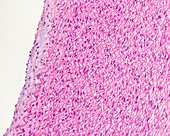

13742427 - Elastic artery, light micrograph

13742425 - Elastic arteries, light micrograph